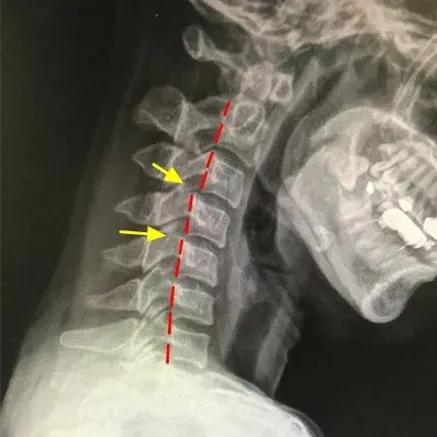

“颈椎有正常的生理弯曲,如果没有生理弯曲,甚至向相反的方向弯曲,称为反弓或反张。该患者本身患有颈椎病,属于颈椎不稳的情况,过山车项目快速的方向变动,更容易诱发颈椎疼痛。”接诊的广医三院中医科主任医师胥海斌解释说。在进行“骨、筋、脉”三联疗法综合治疗后,王女士颈椎疼痛得到缓解。

如果已经得了颈椎病,影像检查报告中,会有“动力性过伸位”“动力性过屈位”的检查项目,这两个项目是决定颈椎安全活动的关键,不同的颈椎病,需要不同的方式来进行康复训练。

如果“动力性过伸位”没有错位,但颈椎侧位片显示颈椎变直甚至出现“反弓”,那么就需要多抬头。